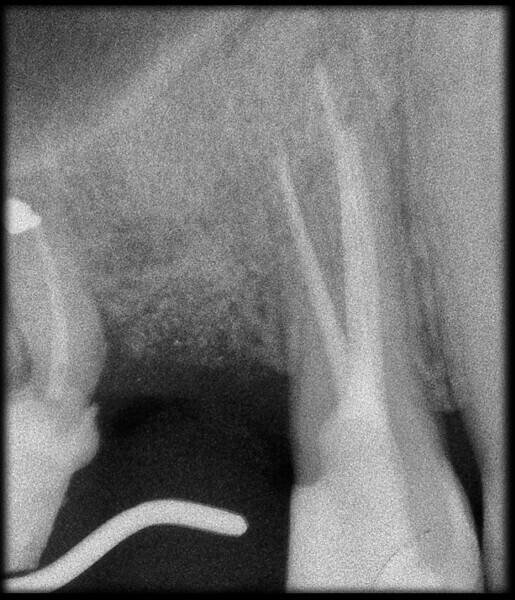

Use of 3D technology in the diagnosis and treatment of endodontic disease